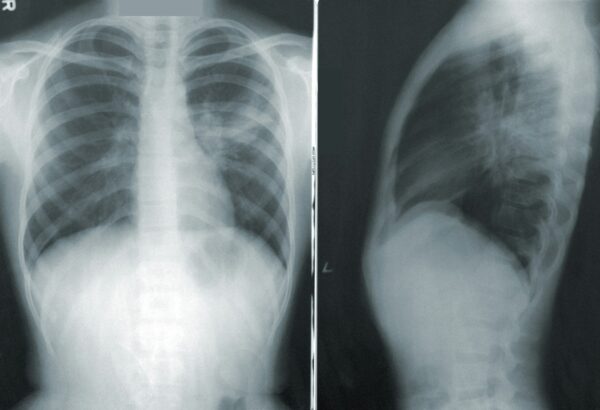

deAndreea Tudor27/05/2025Misterul decesului unui băiat de 17 ani aflat în grija DGASPC Sector 1

Un băiat de 17 ani care era îngrijit în sistemul instituţionalizat din Sectorul 1, mai exact la centrul Buburuza din subordinea DGASPC, a...